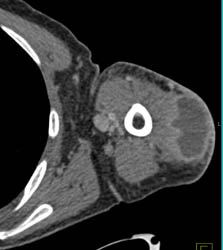

Diagnosis

Tarsal Coalition